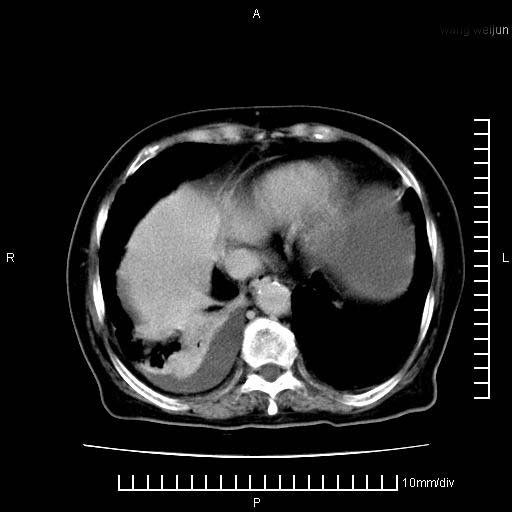

上腹疼痛月余,外院核磁诊断胰腺癌。现临床示右下腹可明显触及包块,可片子上怎么没有看到?

3。右胸腔积液,伴右肺下叶部分萎陷。

1、考虑胰腺癌伴腹膜腔转移,胸腹水。

1)考虑胰腺癌并胰腺假性囊肿形成。2)肝内低密度灶,不排除转移。3)右肾盂积水。4)腹水。5)右侧胸腔积液并右肺下叶部分膨胀不全。

考虑胰腺ca伴腹膜腔转移、肝左叶转移、右肾积水。右胸腔积液。

考虑胰腺ca伴腹膜腔转移、肝左叶转移、右肾积水。右胸腔积液。支持